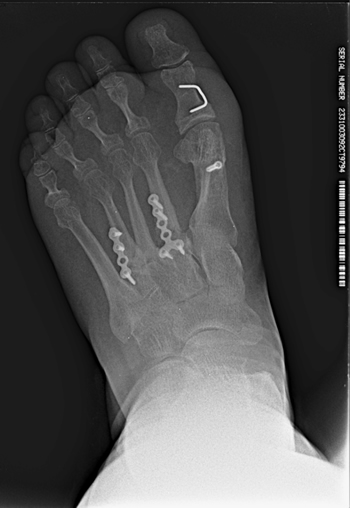

Con fecha 16 de junio de 2015 se realizó la intervención quirúrgica bajo sedación consciente y con anestesia raquídea. Se usaron 2 g de cefazolina intravenosa como profilaxis antibiótica previamente al inflado del torniquete colocado en el tobillo a una presión de 230 mm Hg. Se realizaron cuatro incisiones: una incisión medial para la corrección del hallux abductus valgus, una incisión dorsal sobre segundo metatarsiano, otra incisión dorsal sobre cuarto metatarsiano, y una cuarta incisión en la zona posterior lateral del calcáneo derecho para la obtención del autoinjerto. A través de la primera incisión, se realizó la corrección del hallux valgus con liberación de la contractura lateral vía intrarticular, liberando el ligamento suspensorio y con tenotomías de la cabeza lateral del flexor corto del hallux y del abductor del hallux, junto con osteotomía de Scarf en el primer metatarsiano fijado con un tornillo tipo Herbert (3.0 mm META SCREW® con rosca larga de 20 mm) (Debramedix; Almoradi, Alicante, España) y osteotomía de Akin en la falange proximal (fijado con grapa medial). A través de la segunda incisión en el segundo metatarsiano, se realizó desbridamiento y limpieza de la zona de la pseudoartrosis (Figura 3A). Se midió la longitud del defecto óseo, que era 7 mm, y se obtuvo el autoinjerto de calcáneo del pie derecho (Figuras 4A y 4B) para luego implantarlo en el metatarsiano (Figura 3B). El defecto de calcáneo fue rellenado con sustituto óseo sintético, una cerámica sintética de hidroxiapatita 65 % y fosfato tricálcico 35 % (CERAFORM®, Tecknimed; L’union, France). El autoinjerto de calcáneo utilizado es principalmente de hueso esponjoso y presenta hueso cortical obtenido de las paredes dorsal y lateral del calcáneo, de manera que se situó la porción del injerto con cortical en posición dorsal para resistir mejor las fuerzas de compresión a la carga. Se estabilizó con placa de bloqueo en “T” (miniplaca en T 2/4 orificios 30 x 5 mm con tornillo bloqueado de 2.0 mm) (Debramedix; Almoradi, Alicante, España)(Imagen 8). A través de la tercera incisión se realizó una estabilización del cuarto metatarsiano con placa recta dorsal (miniplaca recta 5 orificios 29 x 5 mm con tornillos bloqueados de 2.0 (Debramedix; Almoradi, Alicante, España). Se realizó finalmente un bloqueo postoperatorio local con 8 ml de bupivacaína 0.5 % junto con 2 cc de betametasona (Celestone®Cronodose®, Schering-Plough; New Jersey, USA). La Figura 5 muestra la radiografía postoperatoria.

Figura 5. Imagen postoperatoria tras la cirugía.

El postoperatorio transcurrió sin incidencias y se realizaron curas postoperatorias con suero fisiológico y povidona yodada a los 7, 21 y 49 días postoperatorios. A las 6 semanas y 2 días (30 de julio de 2015) se realizó TAC de control que fue valorado el 7 de agosto de 2015 (7 semanas y 3 días tras la intervencion). Este TAC evidenciaba buena integración del injerto. Tras este hecho, junto con la favorable evolución clínica, se permitió a la paciente la carga parcial con bota tipo Walker durante 3 semanas para posteriormente comenzar a utilizar calzado convencional de forma progresiva.

A los 5 meses de la intervención se solicitó nuevamente un TAC comparativo que se realizó el 20 de noviembre de 2015 (Figura 6) que evidenció la integración completa del injerto y la consolidación del 4.º metatarsiano. La evolución clínica de la paciente fue muy positiva con ausencia completa de dolor realizando todas las actividades de la vida diaria con normalidad. Con fecha 25 de mayo de 2016 (11 meses postoperatorios) se realizó última visita de la paciente encontrándose esta en perfectas condiciones y dando el alta a la paciente. La paciente ha sido seguido posteriormente con revisiones anuales durante 4 años (hasta 2019) sin ninguna alteración.

Imagen 6. TAC postoperatorio a los 5 meses. 6A. Imagen del 2º metatarsiano que muestra integración del injerto con la placa dorsal. 6B. Imagen del 4º metatarsiano que muestra consolidación del 4º metatarsiano.